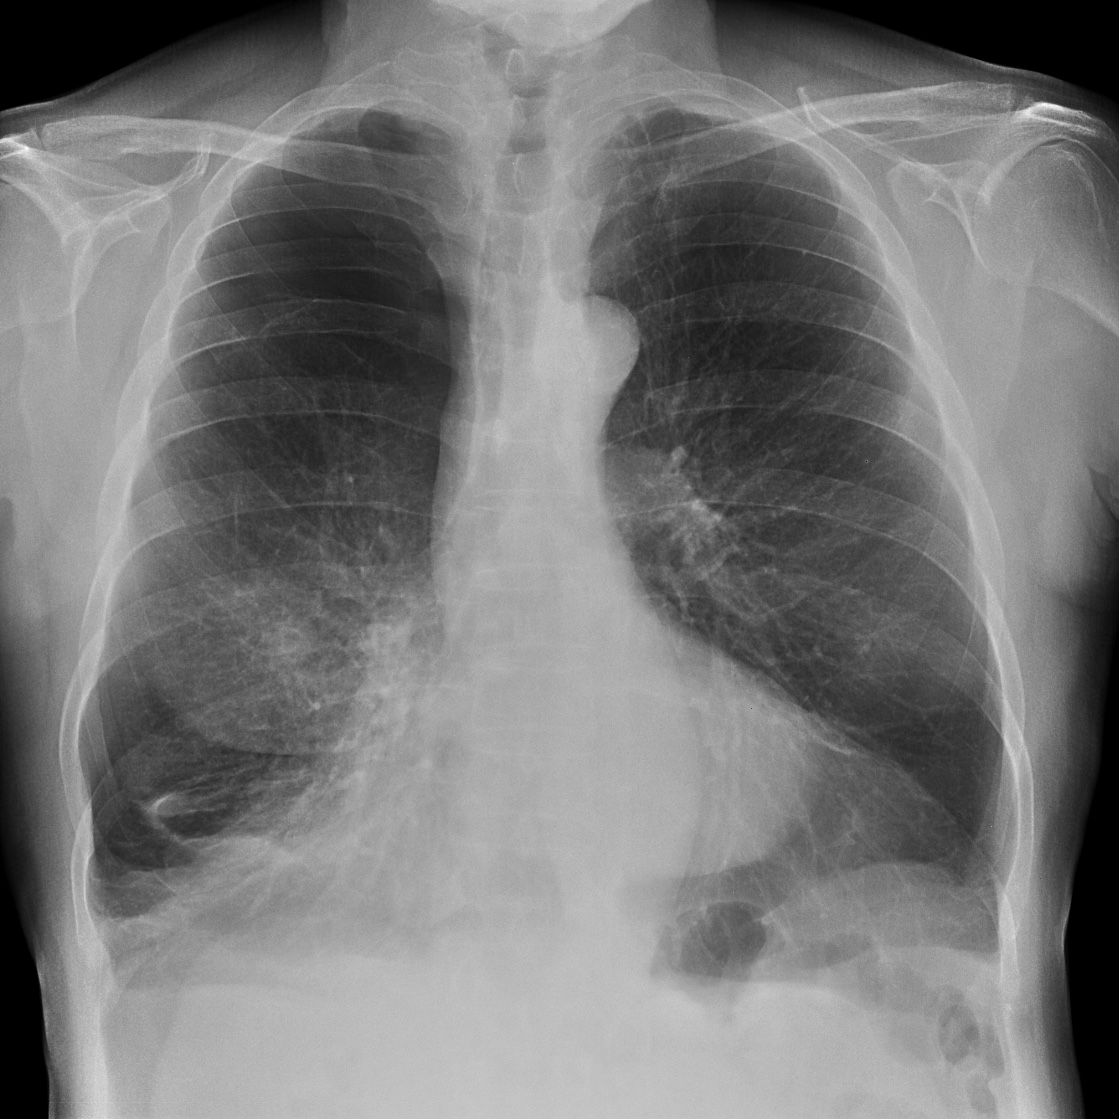

Empecemos, ¿qué ves?

- Comprobar que la placa está bien centrada e inspirada (6 arcos costales anteriores ó 9 posteriores).

- Abdomen y Diafragma

- Partes blandas y estructura ósea.

- Mediastino con silueta cardiaca.

- Parénquimas pulmonares (por separado)

- Comparar un pulmón con otro.

Seguir esta sistemática, dejando el pulmón para el final no nos olvidaremos de lo más importante.

Regla: Acaso Tiene Mucha Patología Pulmonar (Abdomen, Tejidos blandos y hueso, Mediastino, Pulmón por separado, Pulmón bilateral)

Solución: Es un estudio Normal. Silueta cardiomediastínica y parénquimas pulmonares sin alteraciones significativas.